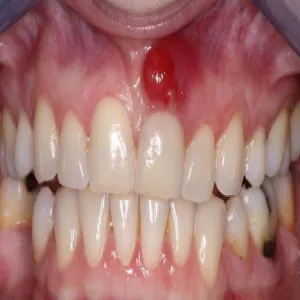

Nadziąślak

Nadziąślak, epulis